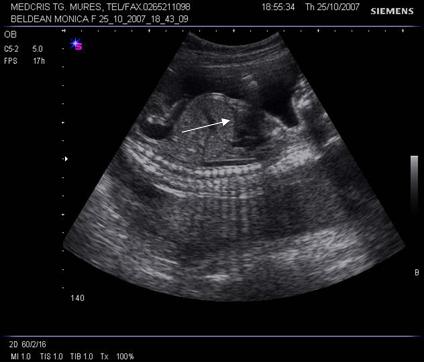

Fig. nr. 175. Sectiune sagitala fetala cu intrarea ductus venosus(sageta ) in vena cava inferioara ( cu linie )